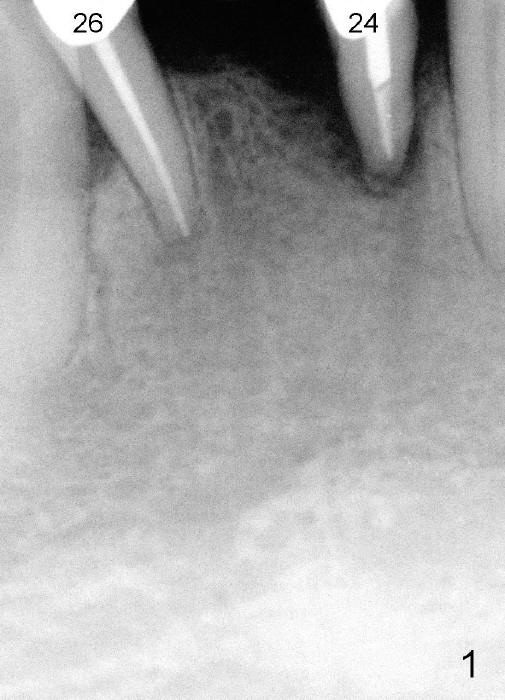

A 67-year-old man has a fixed partial denture (FPD) spanning from #24 to #26 (Fig.1). Originally the abutment #24 has endo perio disease. Finally the tooth #26 fractures. Both of the teeth are extracted and replaced by one piece implants (Fig.2). Placement of the immediate implant at the site of #24 is difficult due to the fact that the socket is deep and that surgical visibility is poor. An incision has to be made for the placement, followed by bone graft and collagen membrane. Tension is released prior to suturing. Two of immediate provisionals are fabricated over the one piece implants and a pontic is bonded to the retainers. Due to deep bite, the pontic is detached quick.

Fig.7 shows these two one piece implants immediately prior to cementation of the FPD (Fig.8). They are much more parallel to each other after prep, as compared to Fig.6. Fig.9 shows apparent bone growth around #24 implant (at the crest) 6,9 months post cementation and surgery, respectively. Orthodontic treatment will incorporate the fixed partial denture. Fig.10 shows that bone grows coronally (arrow) to cover 3 threads (from #6 thread to #3) at the site of #24 one year after functioning. There is mild buccal gingival infection involving #26 retainer. Preop CBCT is reviewed to determine whether it is related to potential thread exposure. It appears that at the sites of #24 (Fig.13,14) and 26 (Fig.11,12), 2.5 mm implant is more appropriate for the narrow ridge than 3.0 mm one. In fact, periimplantitis develops at #26 two years of absence of perio maintenance (because of atrial fibrillation with blood thinner; Fig.15, 3 years 7 months post cementation). Periimplantitis persists 4.5 months later. Although water pik is purchased, it is not used often because of low blowing force. If needed, remove the FPD atraumatically. Unwind the implant, clean the coronal threads with Titanium brush or remove the exposed threads and replant the implant with bone graft.